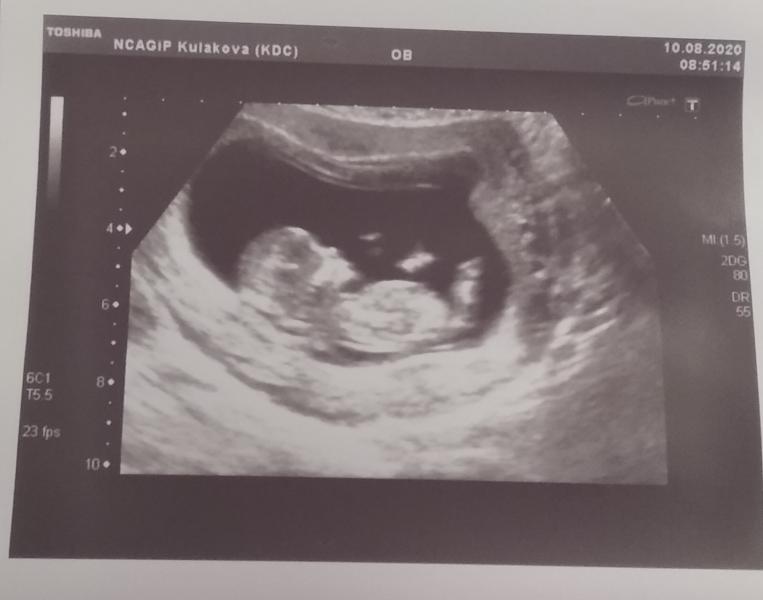

В понедельник сходила на УЗИ и сдала кровь на скрининг. Сегодня забрала результат, риски низкие! УЗИ делала Огай О.Ю., очень понравилась, четко, по делу, доброжелательная. Показала малыша с разных сторон, сказала, что похоже на девочку, но пока не точно. Гематома, которая была на 5-7 неделе, рассосалась, даже выделений не было. В общем, я счастлива!